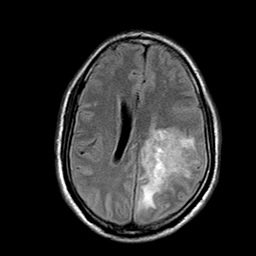

मेरी उम्र 26 साल है मुझे बचपन से लेकर अभी तक किसी भी प्रकार की समस्या नहीं रही है परंतु बीते 2 साल से बाइक के कारण दुर्घटनाग्रस्त हो चुका हूं सन 2015 में जब मेरा एक्सीडेंट हुआ था उस वक्त मेरे उल्टे हाथ की सबसे छोटी उंगली फ्रैक्चर हुई थी उसके ठीक 1 साल बाद 2017 में मार्च 24 को पुनः मेरा बाइक से एक्सीडेंट हो गया. हाथ पैरों मैं चोट आई उल्टे हाथ में काफी सूजन आ गई थी. जब मैं हॉस्पिटल पहुंचा तो वहां सीएमओ के द्वारा X-ray कराने की सलाह दी गई मैंने एक्सरे तुरंत करवाया परंतु सीएमओ के द्वारा एक्सरे में किसी भी प्रकार की फ्रैक्चर का जिक्र नहीं किया उन्होंने यह चीज लिखित में नहीं लिखी थी. मेरे साथ कोई और ना होने के कारण इस चीज पर मैं ध्यान नहीं दे पाया उन्होंने मुझे बताया कि मेरे उल्टे हाथ के टेंडर में चोट आई है जिसके कारण सूजन काफी ज्यादा है और इसको सही होने में 10 दिन से 15 दिन का समय लगता है उसके बाद समस्या ठीक हो जाएगी मुझे लगा कि टंडन में ही अगर प्रॉब्लम है तो धीरे-धीरे ठीक हो जाएगी लेकिन यह समस्या 15 दिन से अधिक होने पर मैं Orthopedics क्टर को दिखाया तब उन्होंने पुनः X-ray कराने की सलाह दी मैंने पुनः एक्सरे कराया और डॉक्टर को दिखाया तब उन्होंने बताया कि फ्रेक्चर इसमें था लेकिन समय पर इसका इलाज ना करने के कारण माल यूनियन हो गया है अब मैं यह जानना चाहता हूं कि इस समस्या के लिए मैं क्या कर सकता हूं और किस प्रकार से समाधान पा सकता हूं क्या भविष्य में इस समस्या के कारण मुझे किसी भी प्रकार की परेशानी आ सकती है अथवा इसके लिए कोई और उपाय करना चाहिए ?

This is my First X ray 24 March 2017